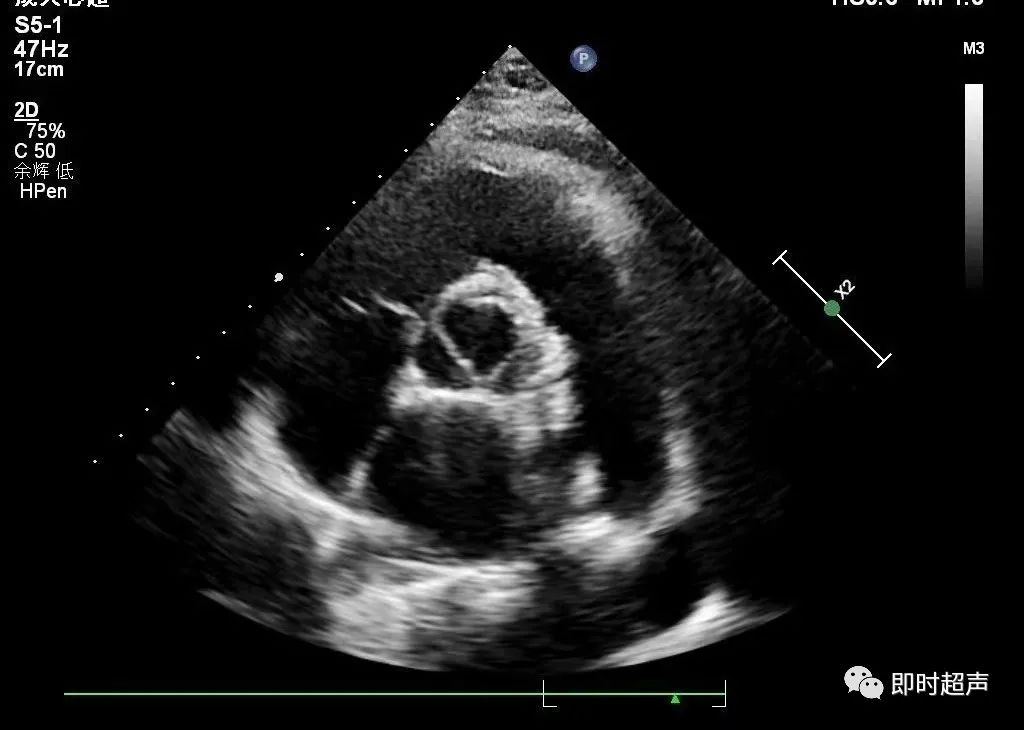

在舒张末期胸骨旁大动脉短轴切面距肺动脉瓣2cm处测量右室流出道内径。